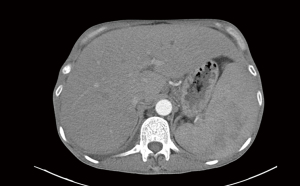

Of the blood tests, (1,3)-β-D glucan assay, cryptococcal antigen, TORCH (toxoplasma, rubella virus, cytomegalovirus, herpes simplex virus), TB-IGRA (tuberculosis interferon-gamma release assay), and multiple blood cultures were negative. The main positive findings were whole blood cytopenia, reduced CD4+ T lymphocyte count, and positive HIV and EBV replication (Table 1). The CT showed a soft tissue shadow in the apical segment of the upper lobe of the right lung, with an area of about 2.5 cm × 2.0 cm, surrounded by patchy shadow and ground glass shadow with a blurred border. The other nodular shadow was scattered in both lungs, partly with cavities, and the largest one was located in the postapical segment of the upper lobe of the left lung, with a length of about 1.0 cm. The large nodules were located in the posterior part of the left upper lobe with a diameter of about 1.0 cm (Figure 1), and an enlarged liver and spleen can be seen (Figure 2). An ultrasound of the lymph nodes suggested large bilateral cervical, supraclavicular, submandibular, bilateral axillary, and bilateral inguinal lymph nodes with structural abnormalities. The gastroscopy results showed multiple longitudinal erosions and ulcers in the lower esophagus, multiple ulcers in the gastric sinus and horn (stage A1), chronic active fundus and corporitis, and distorted and deformed gastric sinus. No biopsy was taken because the patient had extremely low platelets.

The patient subsequently had repeat CT and blood tests. There was a slight improvement in complete cytopenia (Table 2), and the imaging suggested an improvement in the lung infection (Figure 6) and a smaller liver and spleen than before. With stable symptoms, the patient was successfully discharged from the hospital.